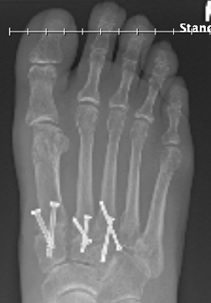

If foot surgery is to be successful, it requires a commitment by the patient. It could require wearing a cast and being non-weight bearing for a considerable period of time. Dr. Leavitt wants you to heal and get the best possible results. As his patient I can attest that the journey is worth it. Dr. Leavitt is truly a gifted and amazing surgeon.

My foot looks absolutely beautiful and feels wonderful! I am back to enjoying my life again. Indeed happiness does start from the feet up.